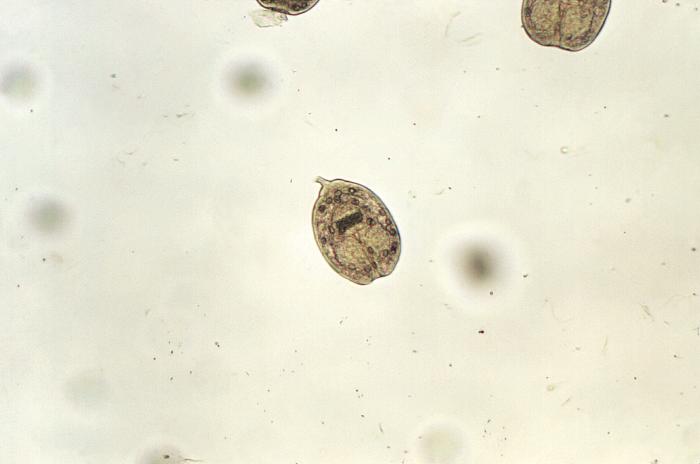

Los huevos son esféricos, miden entre 30-50 micras (μm) de diámetro, están estriados radialmente y en su interior se encuentra la oncosfera (hexacanto) que tiene 6 ganchos retráctiles.